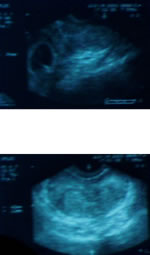

- УЗИ почек - норма

- ТРУЗИ простаты - V=23 см3.